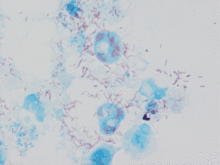

| Rickettsia conorii observed in Vero cells (red rods; magnification ×1,000)[1] | |